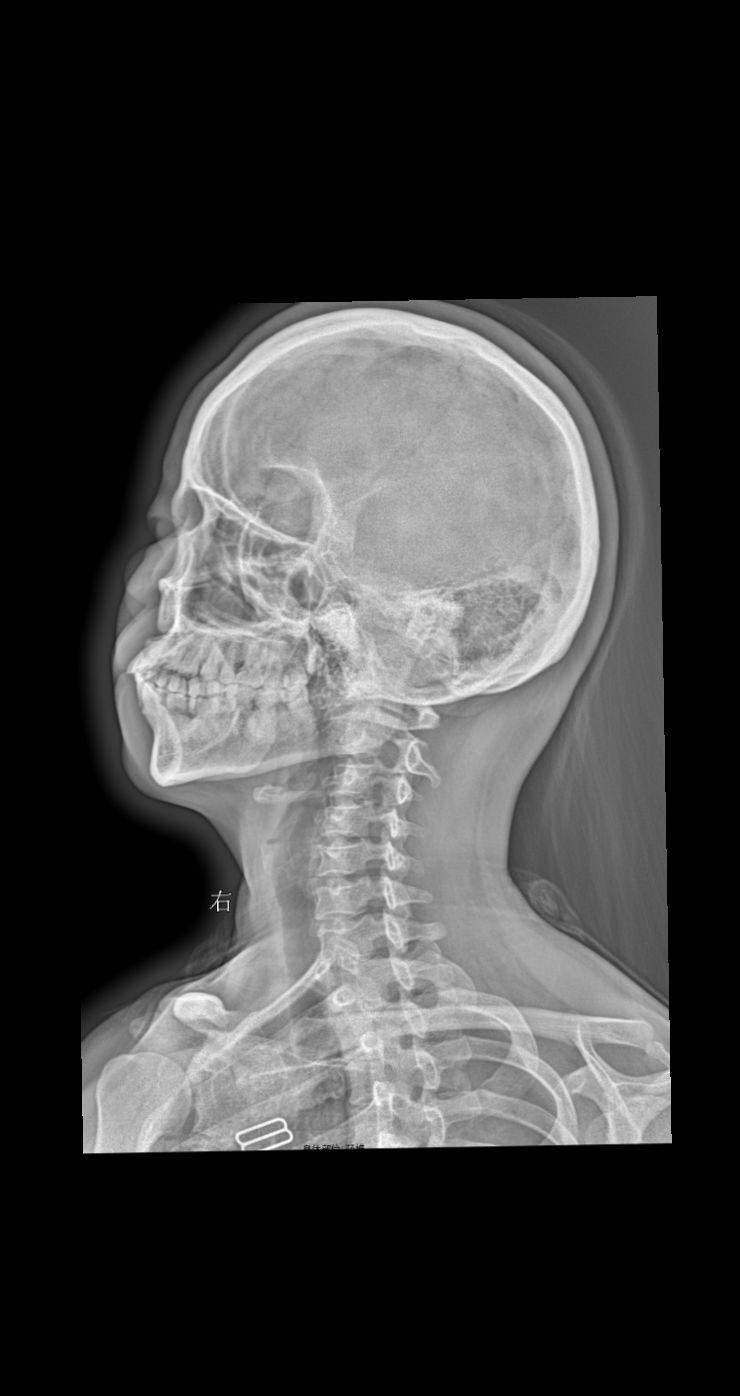

颈部疼痛 头晕 就诊